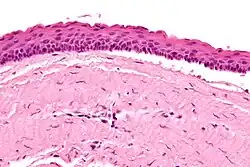

Odontogenic keratocysts have a diagnostic histological appearance. Under the microscope, OKCs vaguely resemble keratinized squamous epithelium;[15] however, they lack rete ridges and often have an artifactual separation from their basement membrane.[2]

The fibrous wall of the cyst is usually thin and uninflamed. The epithelial lining is thin with even thickness and parakeratinised with columnar cells in the basal layer which have focal reverse polarisation (nuclei are on the opposite pole of the cell).[13] The basal cells are an indication of the odontogenic origin as they resemble pre-ameloblasts. The epithelium can separate from the wall, resulting in islands of epithelium. These can go on to form 'satellite' or 'daughter' cysts, leading to an overall multilocular cyst.[10] Presence of daughter cysts is particularly seen in those with NBCCS.[13] Inflamed cysts show hyperplastic epithelium which is no longer characteristic of OKCs and can have resemblance to radicular cysts instead. Due to areas of focal inflammation, a larger biopsy is required for correct diagnosis of odontogenic keratocysts.[10]